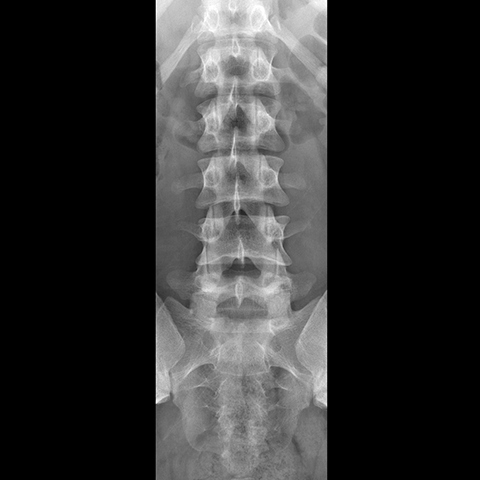

Lumbar Spine, plain film (AP view) [1 of 4]